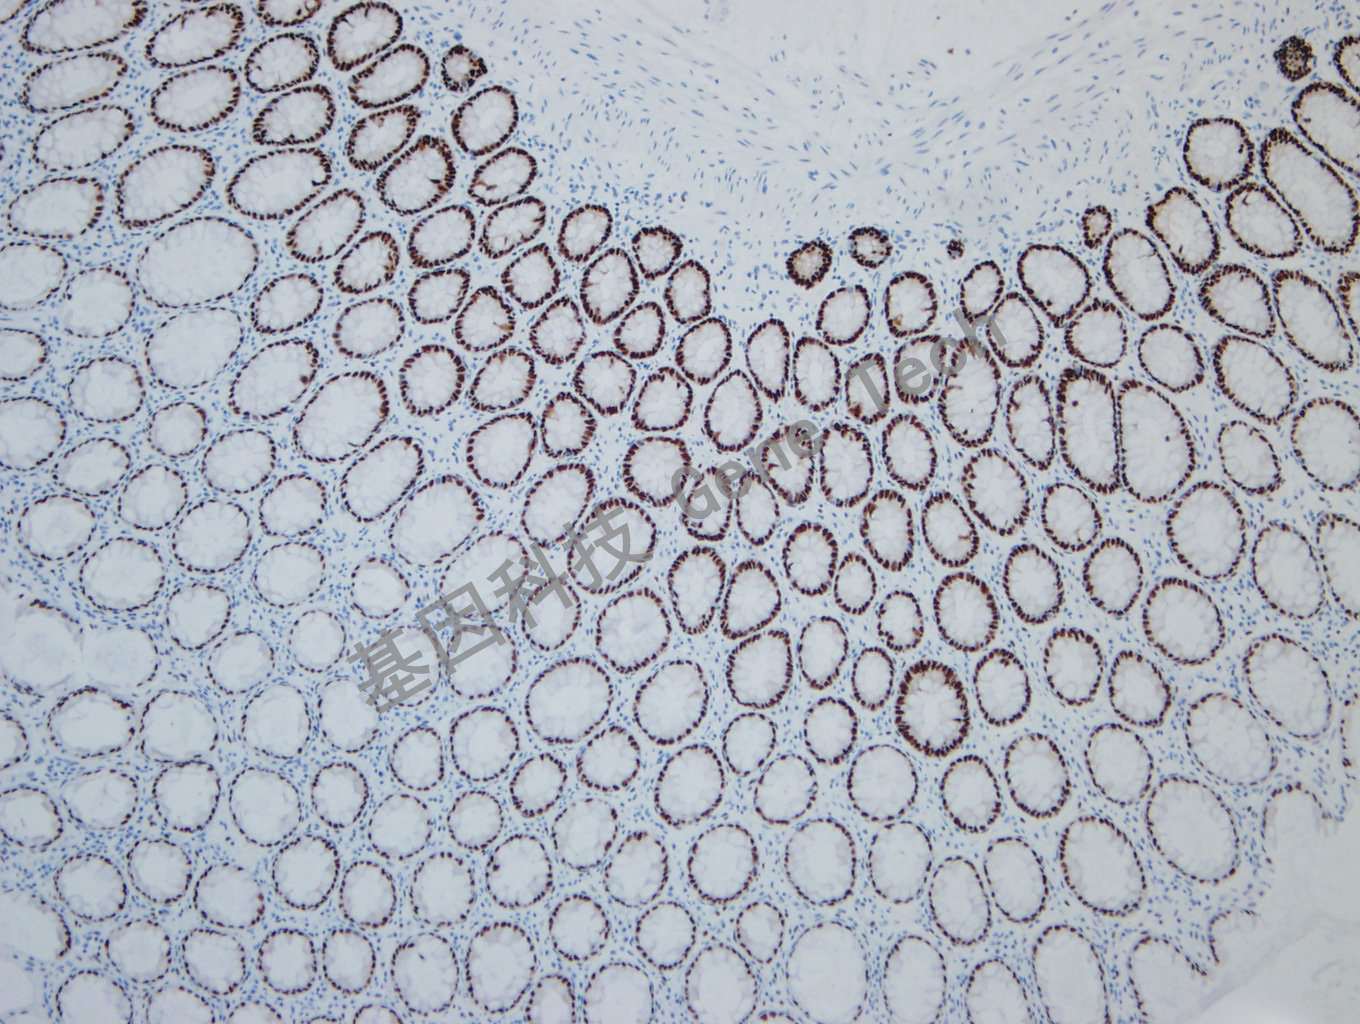

正常结肠石蜡切片,用SOX-9(GT2337)染色,细胞核阳性,DAB 显色。